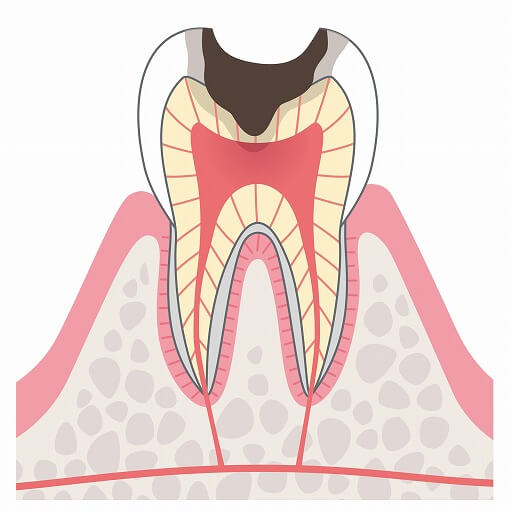

C2

C2はC1より更に進行した状態のむし歯で、エナメル質より下の層の象牙質にまでむし歯が広がってしまった状態です。冷たいものや熱いものが染みることもありますが、このような症状を感じない場合もあります。C2の状態なら3回ほどで治療を終えられることがほとんどです。

C2はC1より更に進行した状態のむし歯で、エナメル質より下の層の象牙質にまでむし歯が広がってしまった状態です。冷たいものや熱いものが染みることもありますが、このような症状を感じない場合もあります。C2の状態なら3回ほどで治療を終えられることがほとんどです。